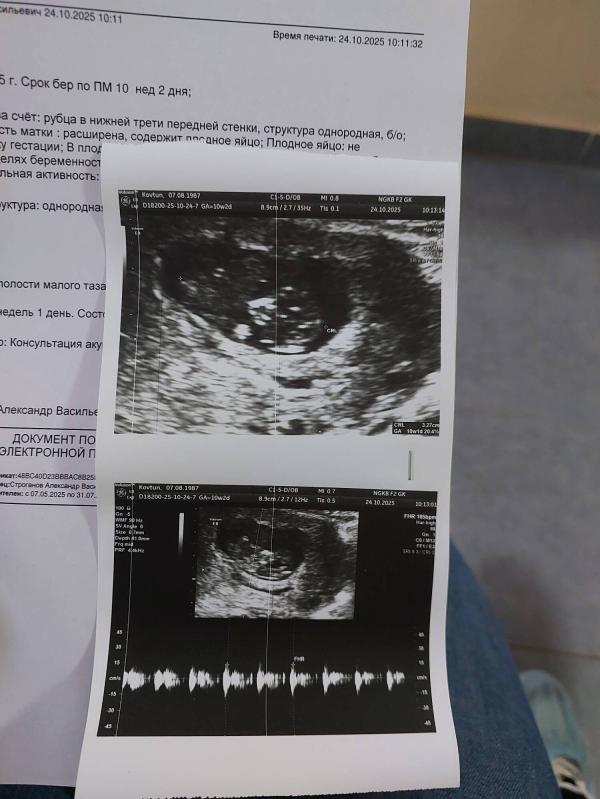

Я так рада, сегодня начался 2 триместр. Токсикоз начал немного отпускать, на скирининг сходила, осталось сдать остальные анализы. Моя крошка, я тебя очень люблю. Эта беременность не без приключений, пришла вставать на учет, врачу показалось, что матка маленькая. Я чуть со стула у них не упала, экстренно отправили на Узи. Врач сразу сделал узи ,включил сердцебиение и показал мне как моя крошка шевелится. Хорошо, что все с ним было хорошо, по срокам все соотвествовало.